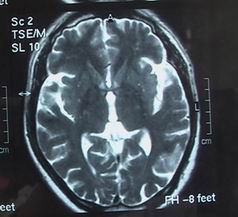

如何调养老年性脑萎缩?老年性脑萎缩是中老年期最常见的一种慢性进行性的疾病,它是由于一种或多种原因导致脑供血供氧不足及脑组织体积缩小和脑细胞数目日渐减少引起的记忆力减退、情绪不稳、思维能力减退、注意力不能集中、严重时发展为痴呆、语言障碍、终至智力丧失等为其临床特征。 本病多发于50岁以上的患者,病程可逾数年甚至10余年,女性多于男性。

脑萎缩是"老年性脑萎缩",是一种老年人脑子老化的表现。关于治疗和保养,应注意下列几方面: